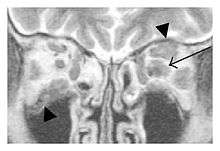

The extent of inflammation that can occur in IgG4-ROD is well demonstrated on magnetic resonance imaging (MRI).

Infraorbital nerve enlargement (IONE) is considered to be a particularly suspicious sign of IgG4-ROD, but seems to occur only when inflammation is in direct contact with the infraorbital canal.[10] IONE is defined as the infraorbital nerve diameter being greater than the optic nerve diameter in the coronal plane.

![]() Swelling of the left superior and lateral rectus muscles, a mass lesion around the left optic disc (arrow), and enlargements of the left supraorbital nerve and the right infraorbital nerve (arrow heads) in a 60-year-old man with a serum IgG4 of 463 mg/dL.[1] (T1-weighted MRI) |